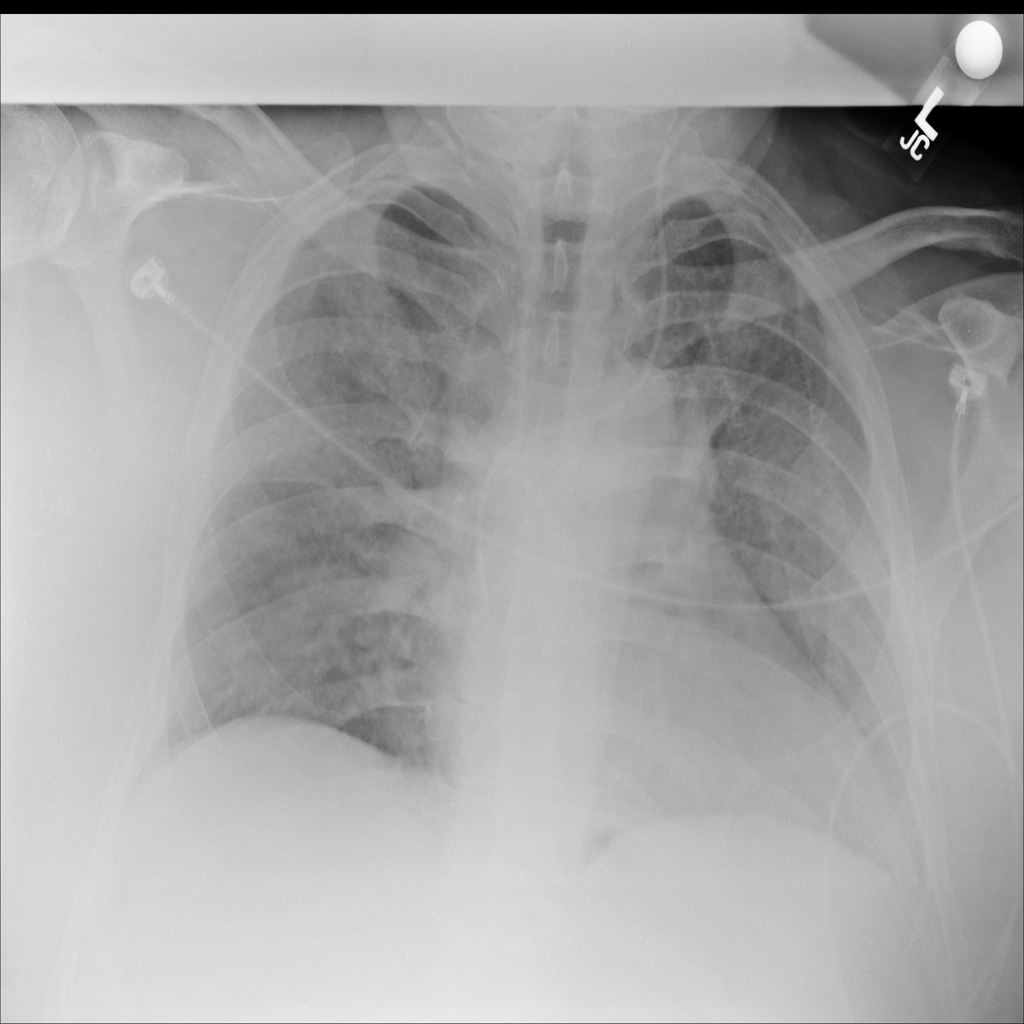

PAT-5B86 · IMG-009Edema

PAT-5B86 · IMG-009

PA